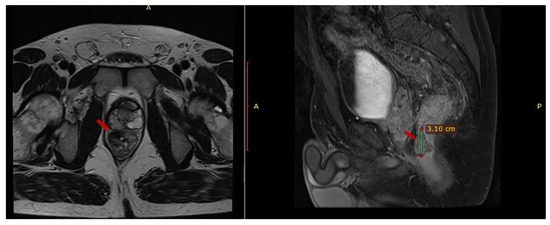

An abdominal and pelvic MRI was performed in March 2023 and it identified circumferential parietal thickening of the rectal wall (1.2 cm), a fibrous lesion with microcalcifications (2.8 × 1.47 × 3.08 cm) adherent to the prostate, multiple mesorectal lymphadenopathies (up to 1.25 cm) and (1.97 × 0.87 × 1.7 cm) thick fluid collection located in contact with the anterior portion of the prostate (Figure 1).

Figure 1. Pelvic MRI axial T1 and sagittal T2 sequences depict contrast-enhanced fibrous tissue in the rectum that adheres to the prostate.